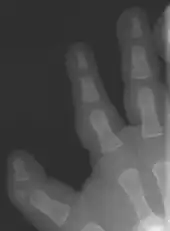

In combination with polydactyly

Delta shaped extra phalanx

There are multiple classifications for the triphalangeal thumb. The reason for these different classifications is the heterogeneity in appearance of the TPT. The classification according to Wood [9] describes the shape of the extra phalanx: delta (Fig. 4), rectangular or full phalanx (Table 1). With the classification made by Buck-Gramcko a surgical treatment can be chosen (Table 1). Buck-Gramcko differentiates between six different shapes of the extra phalanx and associated malformations.[10]